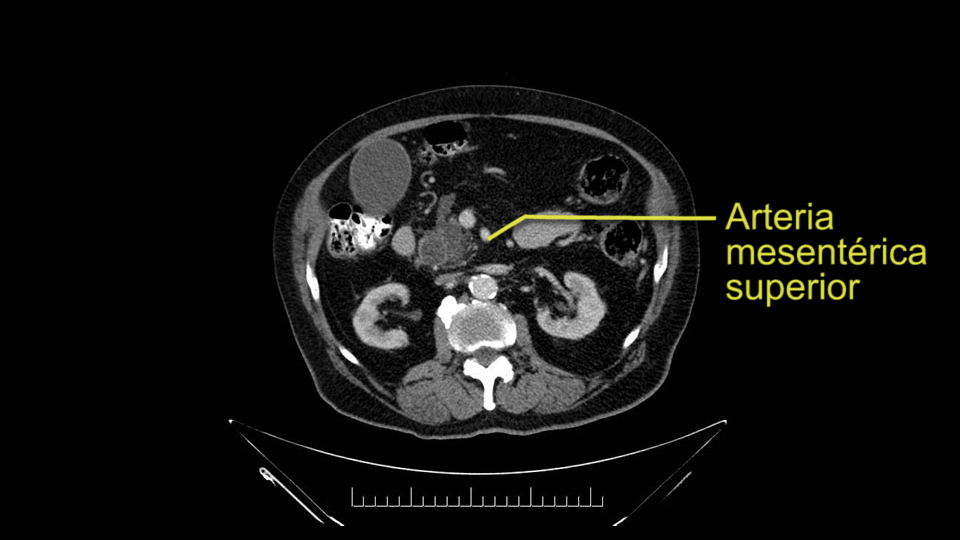

Then either through the coronal or the axial, I’ll do both. Look at the SMA -which is here- I had already looked at it and I don’t see any involvement. There’s the SMA with a nice fat plane between the SMA and the tumor. Over here you can see on the axial, there’s the SMA. Everything on the right side of the SMA has got some nice black around it, which is fat, which means probably no tumor [no tumor, no tumor]. Follow it up to the origin, coming off the aorta. So those are the two technical things that I worry about: the SMA and the SMV.

To plan a pancreatoduodenectomy, we start by reviewing the vascular anatomy, especially the origin of the celiac trunk, here, in front of the aorta, looking for any evidence of stenosis. In addition, we look at the origin of the superior mesenteric artery, to look for any branches, and any replaced right hepatic arteries coming from the superior mesenteric artery; which does occur in about 12% of the population.

Other important points are: the dissection of the uncinate process which must be done very carefully, the ligation of the venous branches there, and looking for the inferior pancreaticoduodenal arteries coming from the superior mesenteric artery during the dissection of the uncinate process.

Para planear una pancreatoduodenectomía, se debe revisar la anatomía vascular, especialmente el origen del tronco celíaco, aquí, por delante de la aorta, buscando areas de estenosis y por otro lado, el origen de la arteria mesentérica superior, para evaluar -sobre todo- si hay ramas, arterias hepáticas derechas provenientes de la mesentérica superior; lo cual ocurre en alrededor del 12% de la población.

Otros puntos importantes por supuesto son: la disección del proceso uncinado, que debe ser muy cuidadosa, la ligadura de las ramas venosas, la búsqueda de la arteria pancreaticoduodenal inferior, proveniente de la arteria mesentérica superior, durante la disección del proceso uncinado.

Uncinate margin, IPDA

Once the pancreatic neck is divided, you sort of roll or flip the neck of the gland over, exposing the anterior surface and the right lateral surface of the portal vein-SMV complex. Continue that dissection down. Oftentimes you can really continue your dissection right along the uncinate on the SMA. Again a little advantage of this patient having an ampullary lesion, there's likely to be no evidence of extension into the uncinate so you don't have to worry quite as much about the margin at the uncinate as you would with a pancreatic head cancer. Keeping in mind that you will have an inferior pancreatic duodenal artery in there that you want to try to identify and ligate individually. At some point along that time I go to the ligament of Treitz. Clean an area of the ligament of Treitz of its mesentery, divide it there with a linear stapler. I use the Harmonic scalpel to mobilize the proximal 10-inches or so of small intestine down to the ligament of Treitz completely mobilize the ligament of Treitz past the jejunal limb underneath the root of the mesentery and then carefully dissect the third and fourth portion of the duodenum’s mesentery as well as the remaining uncinate to complete my resection. I will have marked and sent frozen section from the pancreatic neck at the time that I do the resection of that part of the gland so that I have that information back by now. I would also probably get a margin on the uncinate and a margin on the bile duct just for completeness, although for an ampullary carcinoma that would be unlikely to have a positive extension.